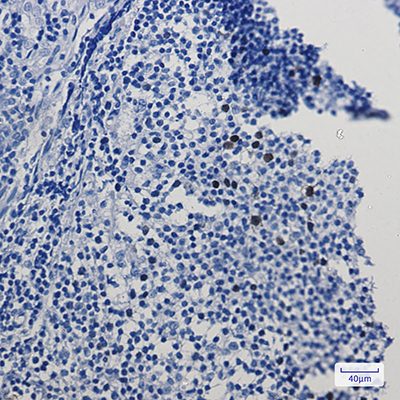

WB,IHC-F,IHC-P,ICC/IF,IP

WB: 1:500-1:1000 IHC: 1:50-1:100 IF: 1:50-1:200 IP: 1:20